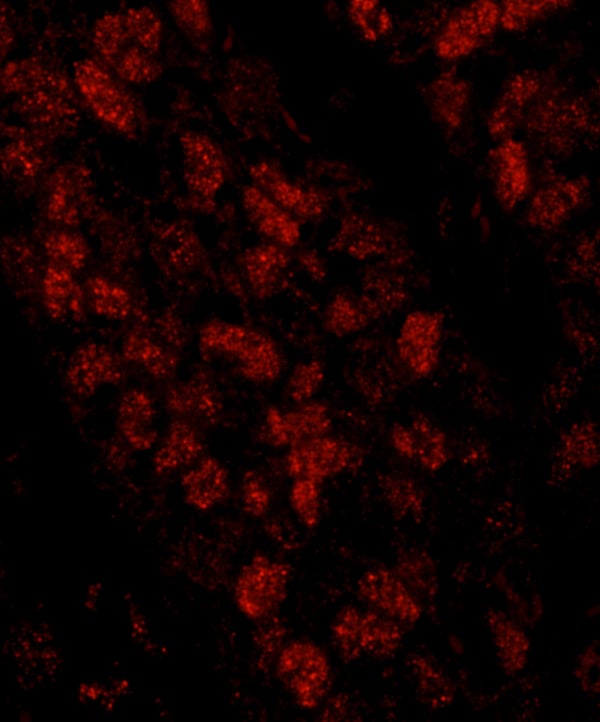

(Detection of human CTF18 by immunohistochemistry. Sample: FFPE section of human breast carcinoma. Antibody: Affinity purified rabbit anti-CTF18 (Cat. No. AAA213984) used at a dilution of 1:100. Detection: Red-fluorescent goat anti-rabbit IgG highly cross-adsorbed Antibody used at a dilution of 1:100.)